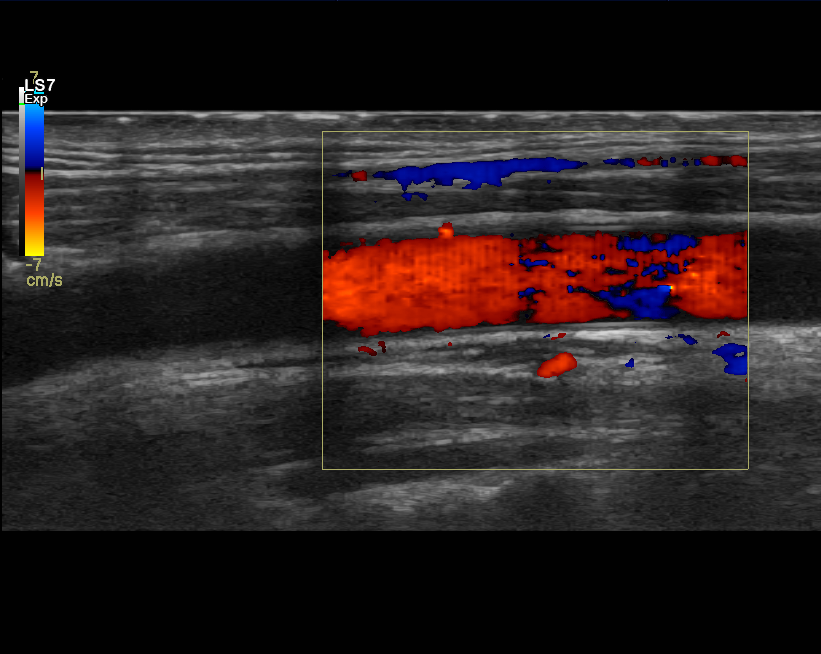

Kaulavaltimoiden ultraäänitutkimus

Kaulavaltimoiden verenvirtausta voidaan arvioida ultraäänellä, erityisesti silloin kun epäillään suonen ahtaumaa tai tukosta. Tällainen muutos voi heikentää aivojen verenkiertoa ja aiheuttaa erilaisia oireita. Kaulavaltimoiden ultraäänitutkimus on turvallinen, nopea ja vaivattomasti toteutettava.

Seuraavaksi lääkäri liikuttaa ultraäänianturia kaulalla ja tarkastelee samalla näyttöä, josta nähdään kaulavaltimoiden rakenne ja verenvirtaus. Tutkimuksen aikana lääkäri selittää usein havaintojaan ääneen. Tampereen Ultrassa voit myös itse esittää kysymyksiä tarvittaessa.